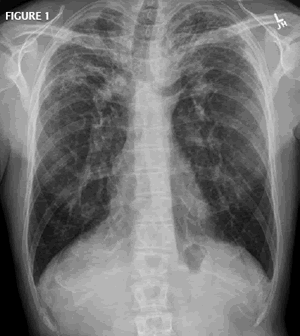

CXR: What is the finding and DDx?

UPPER ZONE FIBROSIS:

DDx: CHARTSs

1. Chronic Extrinsic Allergic Alveolitis

2. Histocytosis X (No volume Loss)

3. Ankylosing Spondylitis

4. Radiation

5. TB

6. Sarcoidosis

7. Silicosis